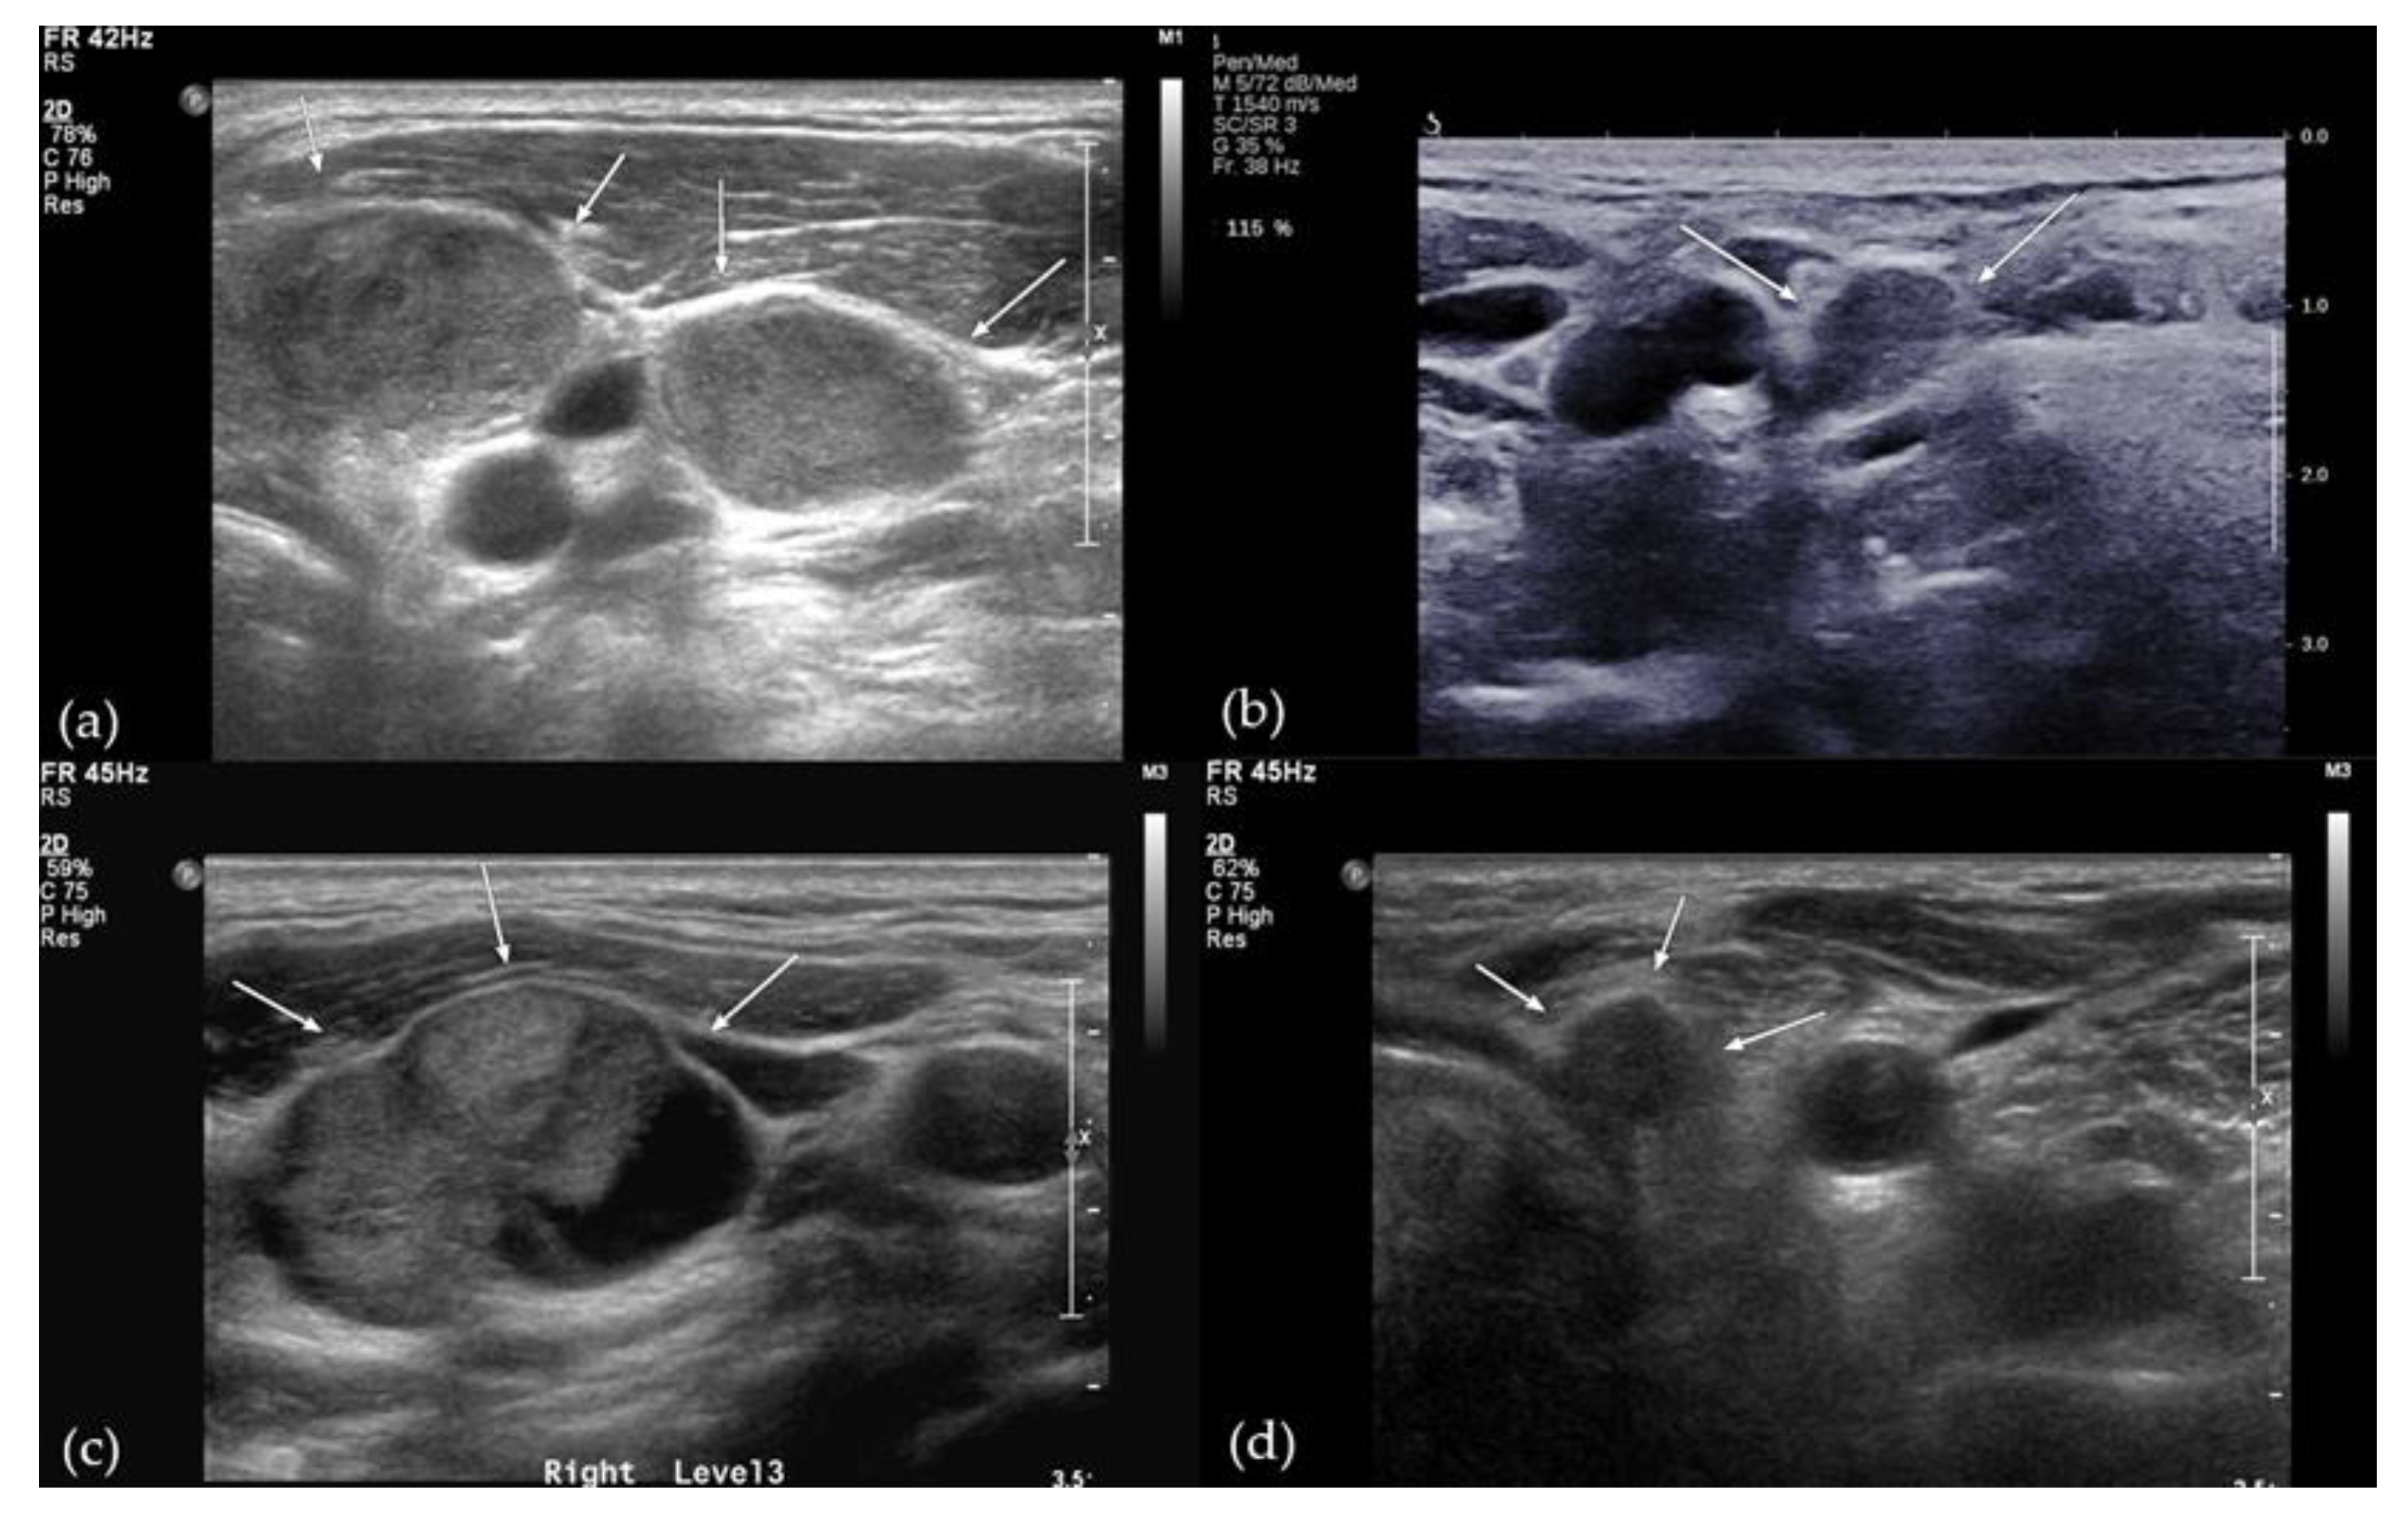

2.2. Image Analysis

| LN echogenicity | <0.0001 | ||

| Hypo-/isoechogenicity | 250 (38.2) | 2 (5.4) | |

| Hyperechogenicity | 405 (61.8) | 35 (94.6) |